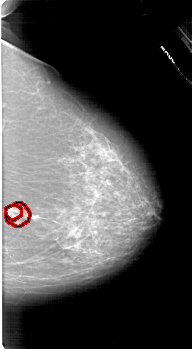

A_1618_1.RIGHT_MLO

RIGHT_CC LINES 6616 PIXELS_PER_LINE 3631 BITS_PER_PIXEL 12 RESOLUTION 43.5 OVERLAY

RIGHT_MLO LINES 6301 PIXELS_PER_LINE 3661 BITS_PER_PIXEL 12 RESOLUTION 43.5 OVERLAY

FILE: A_1618_1.RIGHT_MLO.OVERLAY

TOTAL_ABNORMALITIES 1

ABNORMALITY 1

LESION_TYPE MASS SHAPE IRREGULAR MARGINS SPICULATED

ASSESSMENT 5

SUBTLETY 3

PATHOLOGY MALIGNANT

TOTAL_OUTLINES 2